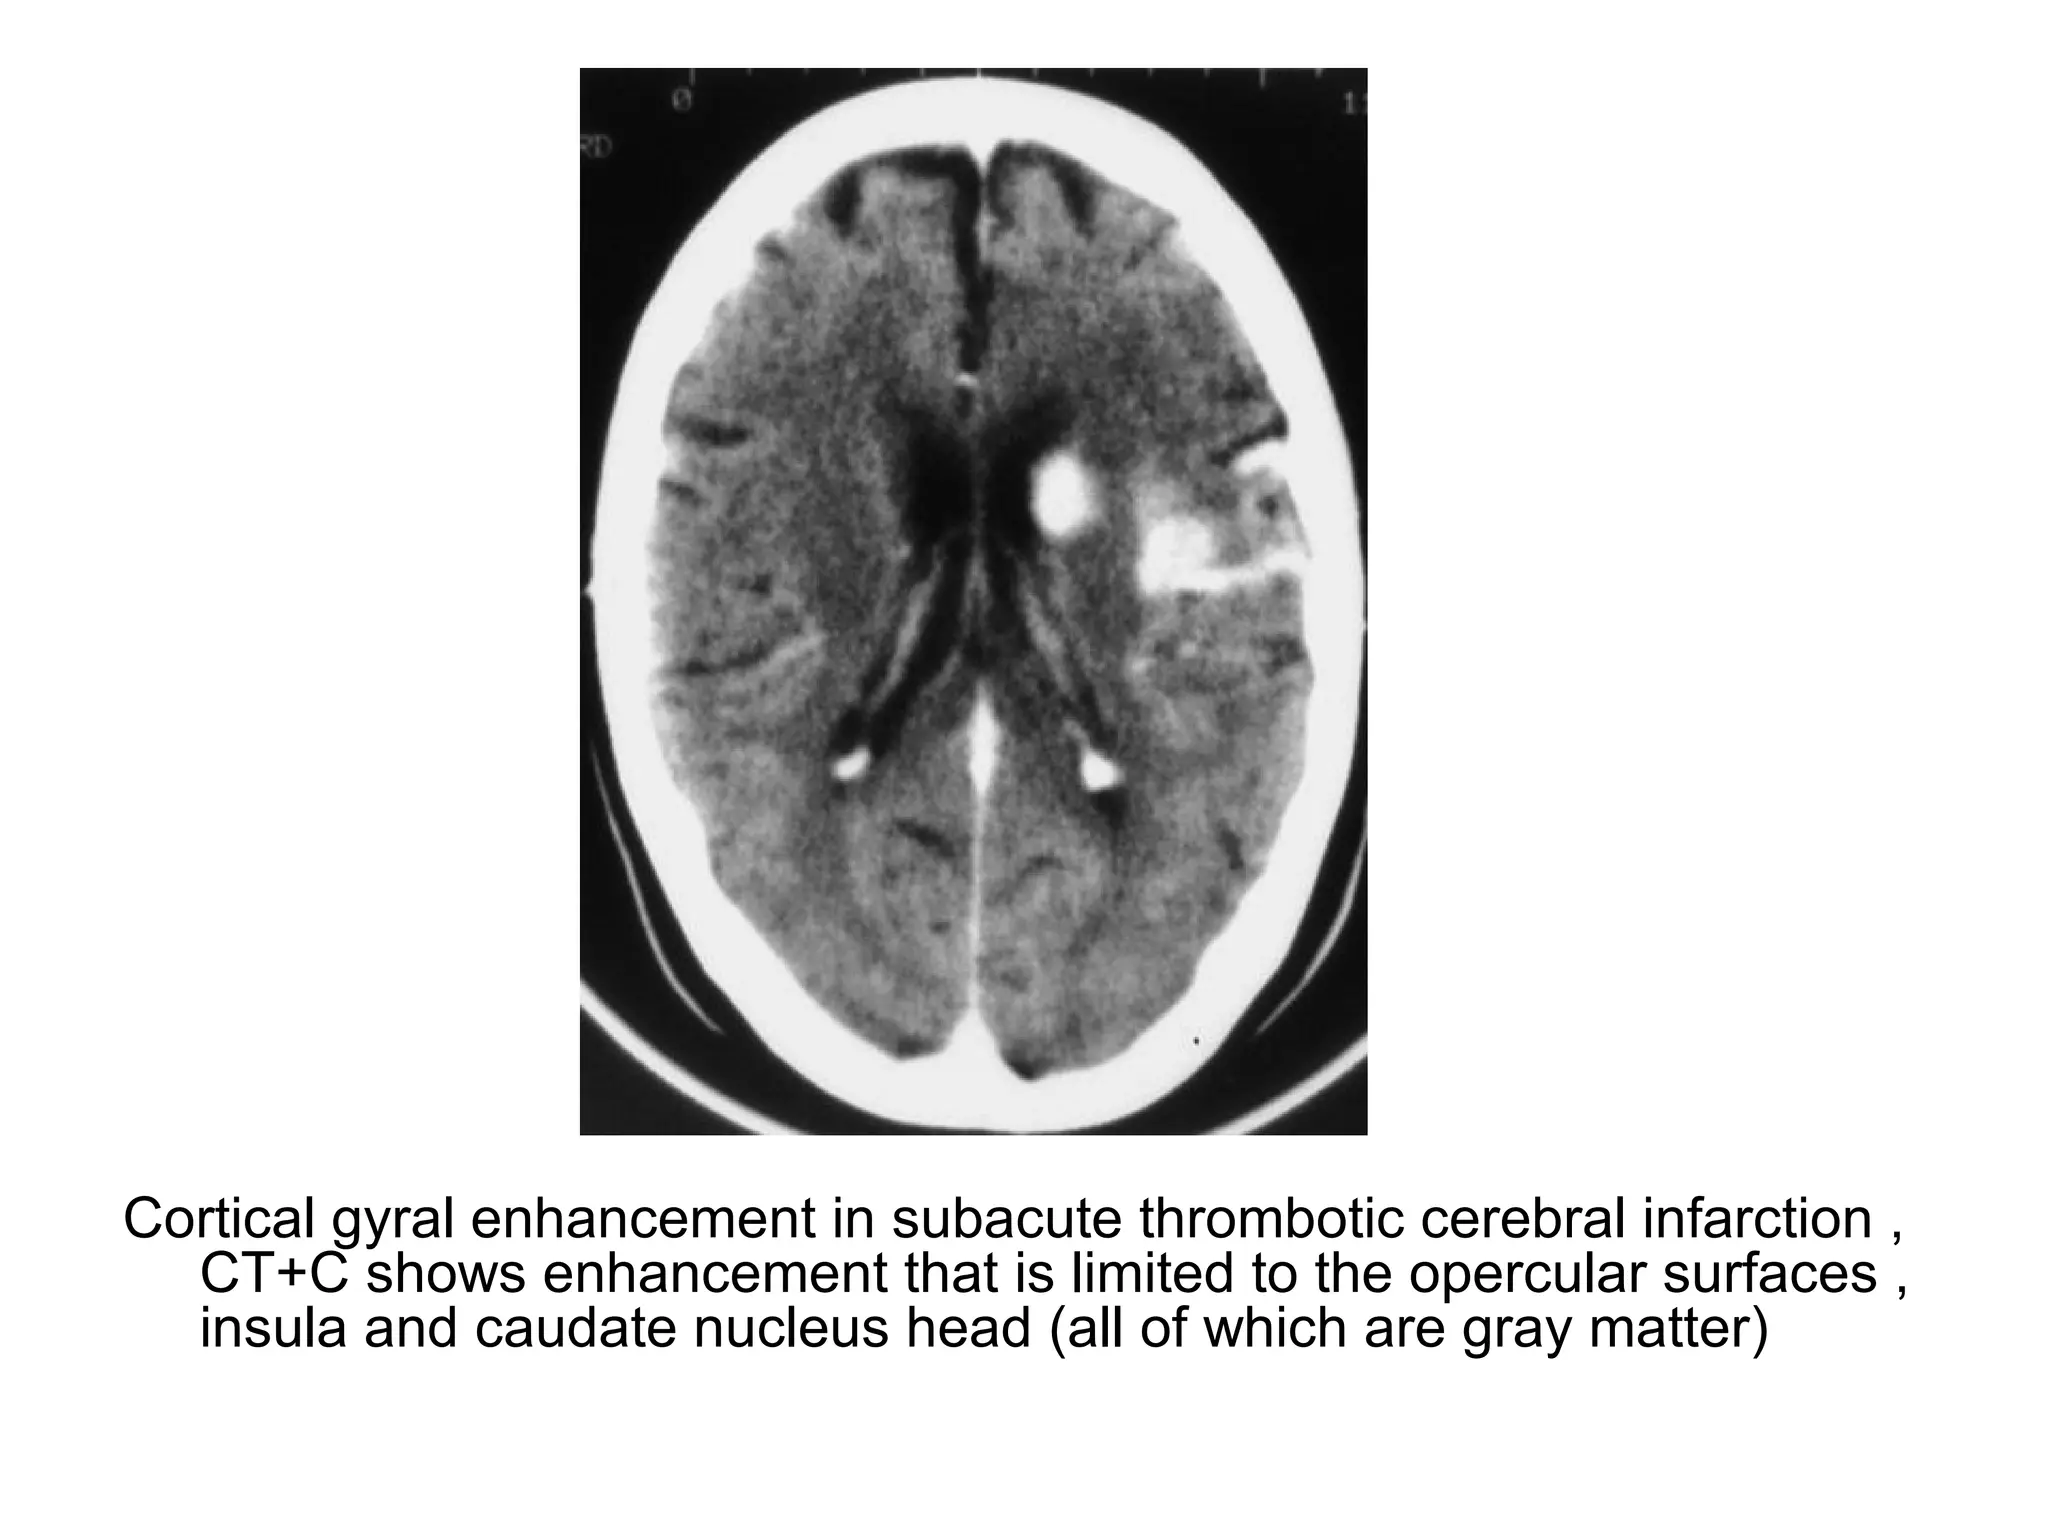

Cortical gyral enhancement in subacute thrombotic cerebral infarction ,

CT+C shows enhancement that is limited to the opercular surfaces ,

insula and caudate nucleus head (all of which are gray matter)